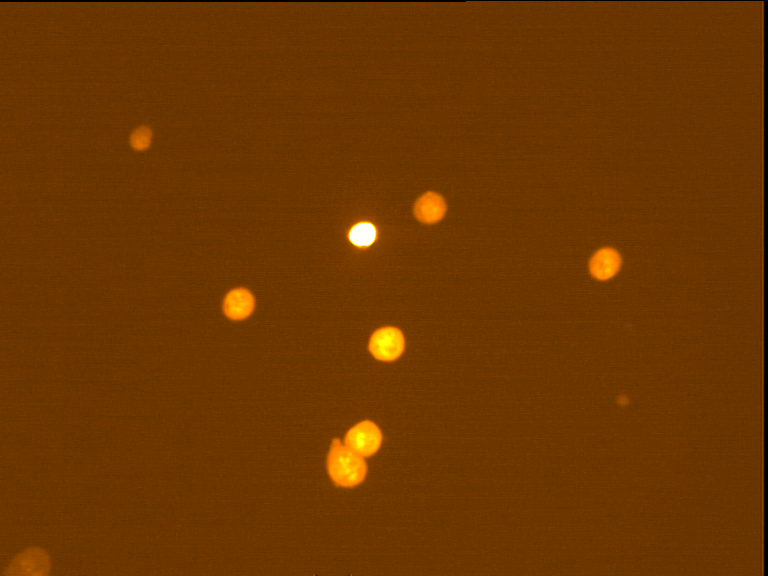

Fig. 4 through 6 show the morphological features of Raji cell sub-lines exposed to DOX, indomethacin, or verapamil. Some of the reversal agents significantly increased the frequency of apoptotic cells compared with control cells. Thus, the P-gp reversal agents were able to overcome apoptotic resistance in the NHL cell-line model. Apoptotic cells in the controls contributed approximately 10% of the whole population (i. e., 61/600 x 100 = 10.16% for TK+ and 69/600 x 100 = 11.5% for TK-). After exposure to the P-gp reversal agents, apoptic cells increased to 22.3% with indomethacin and to 43% with doxorubicin in TK+ cells. In TK- cells, apoptic cells increased from 11.5% to 26.8% and 75.7% with indomethacin and doxorubicin, respectively.

Fig. 5: Morphological features of Raji TK+ cells after treatment with indomethacin (1), verapamil (2) and DOX (3). In each row, left images show intact cells, middle images show apoptotic cells, and right images show necrotic cells as they appeared under the microscope X 200

Fig. 6: Morphological features of Raji TK- cells after treatment with indomethacin (1), verapamil (2), and DOX (3). In each row, left images show intact cells, middle images show apoptotic cells, and right images show necrotic cells as they appeared under the microscope X 200